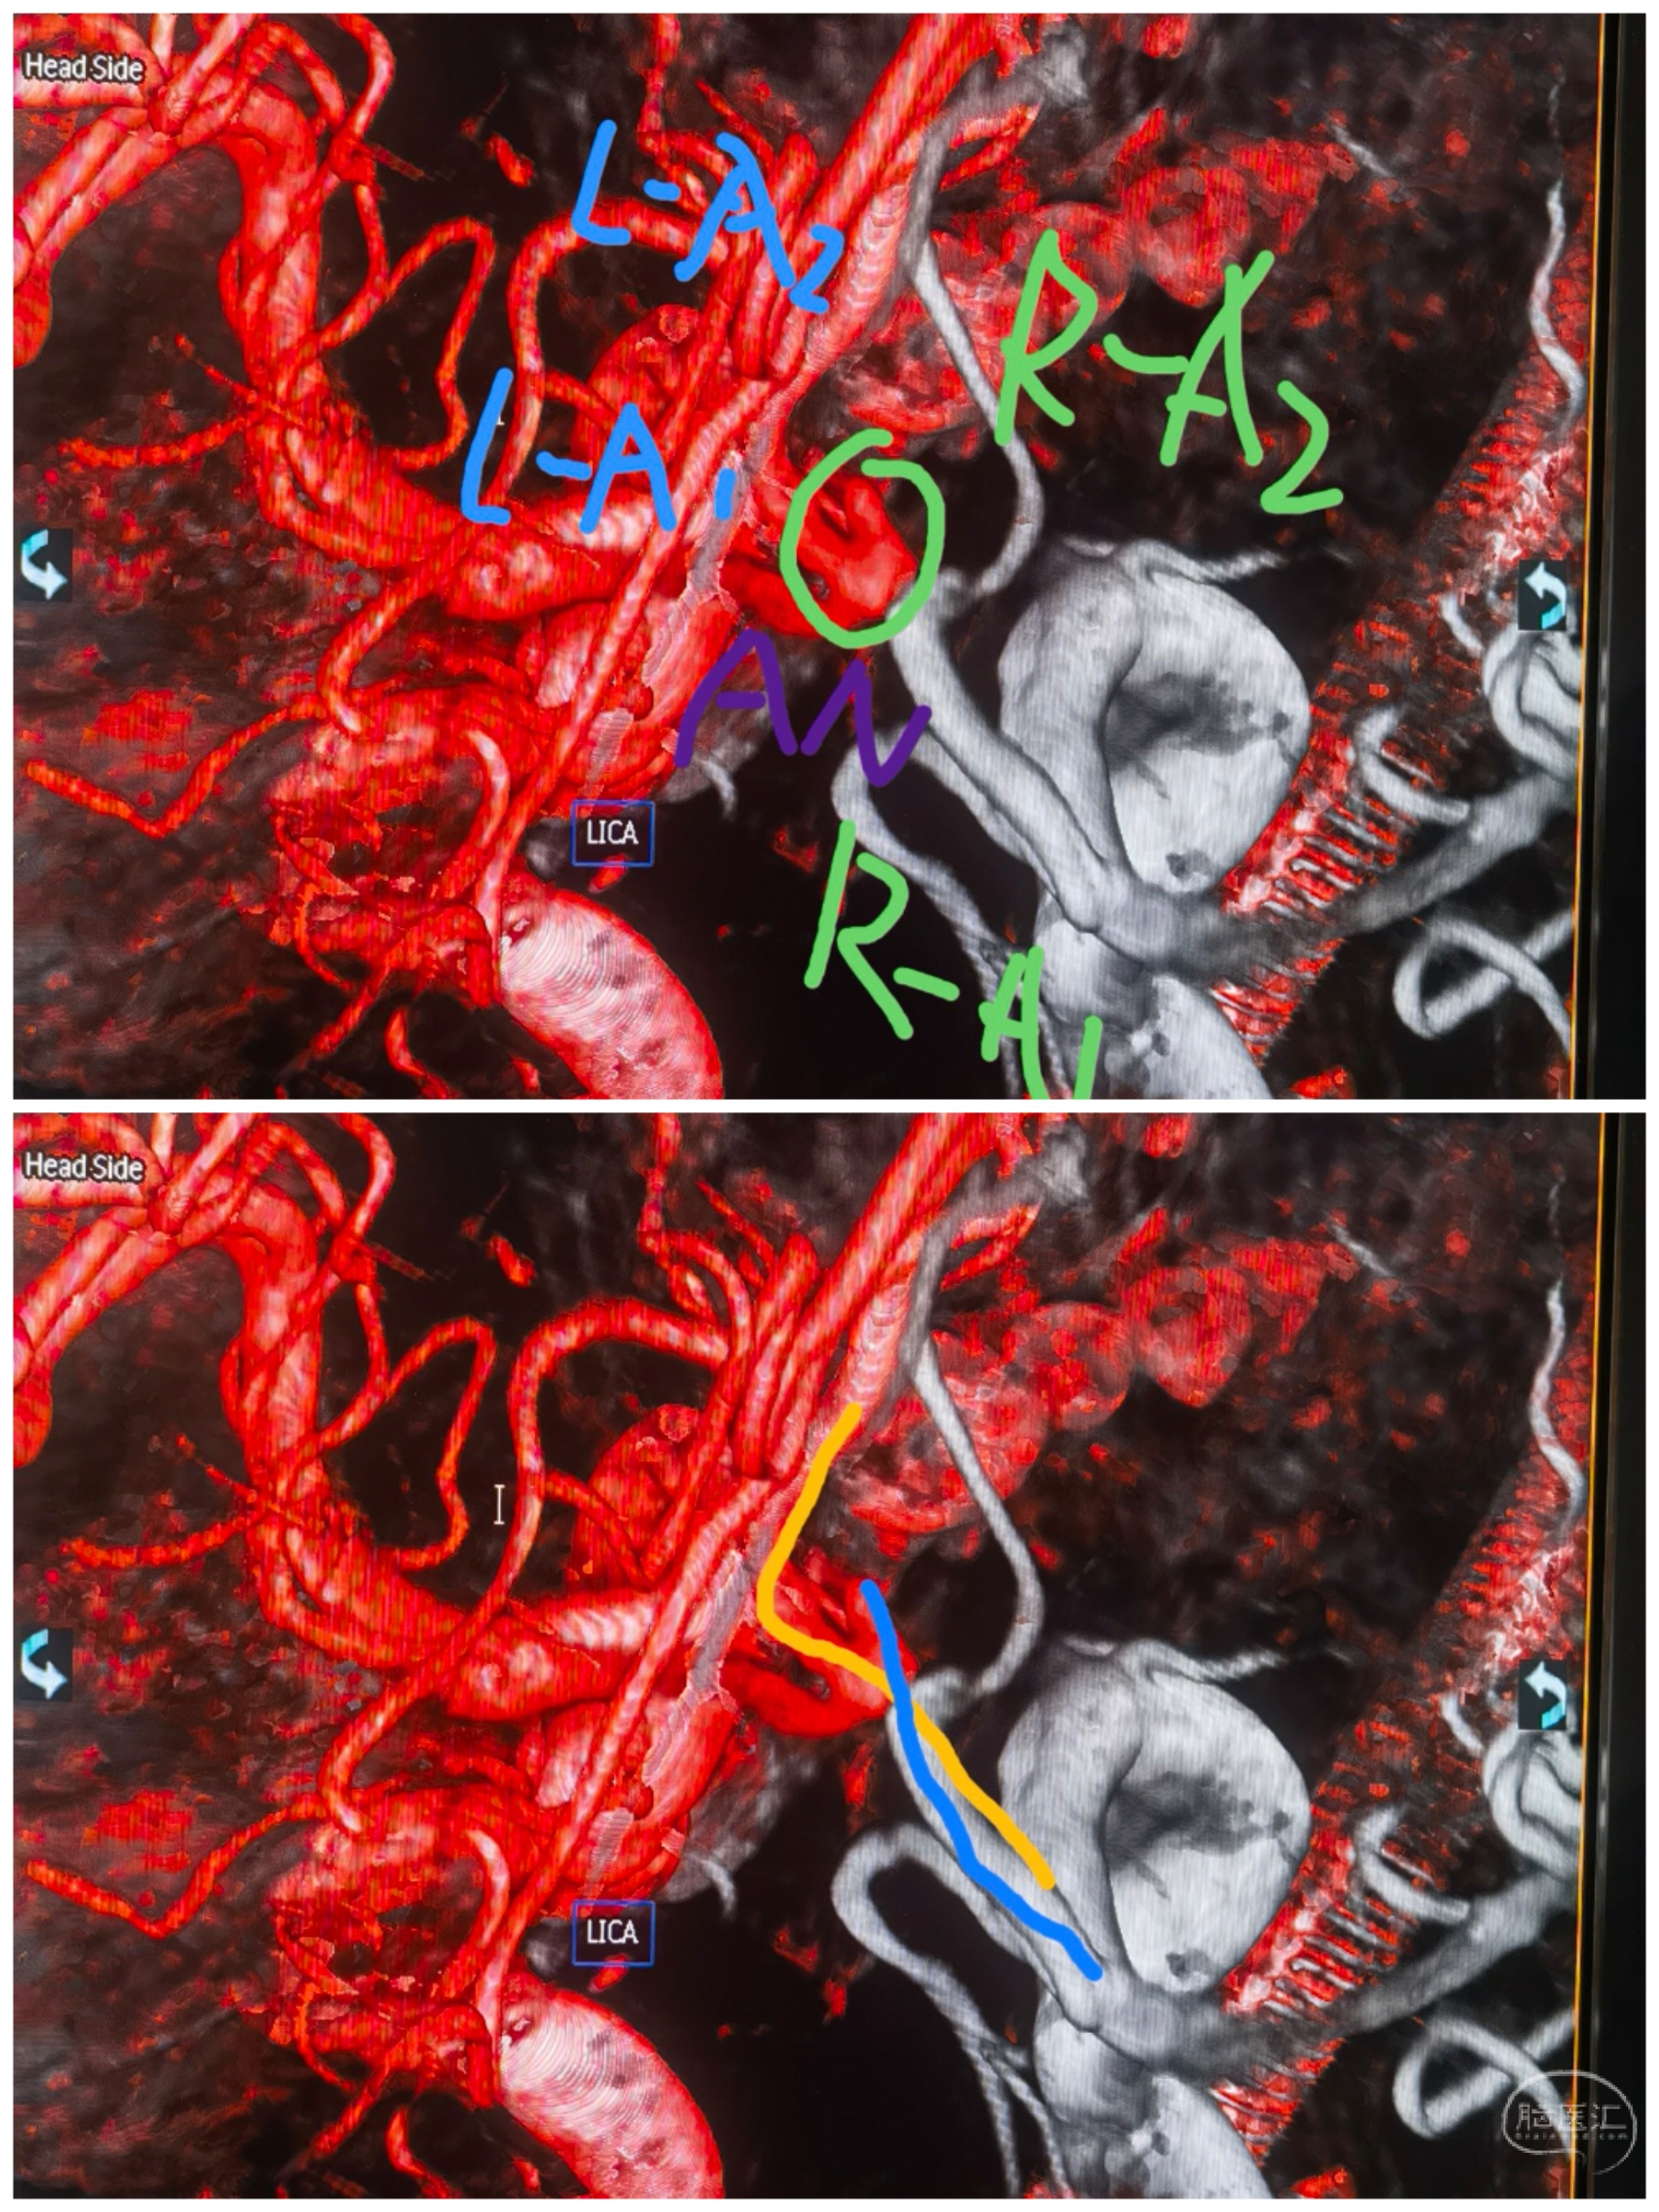

3D重建

双侧颈内3D融合

结构分析

最初手术计划:左侧大脑前优势,左颈内造影前交通动脉瘤显影。拟经左侧通路治疗,左侧A1-左侧A2释放支架导管,左侧A1释放栓塞微导管。无奈左侧A1-左侧A2夹角锐利,支架导管无法通过😂😂

还好术前龙哥远程指导提醒了下,可以经右侧A1-前交通-左侧A2走支架导管。果断更换思路,经右侧通路,双侧同时路途。经右侧A1-前交通-左侧A2支架导管,右侧A1栓塞导管直接指向动脉瘤。